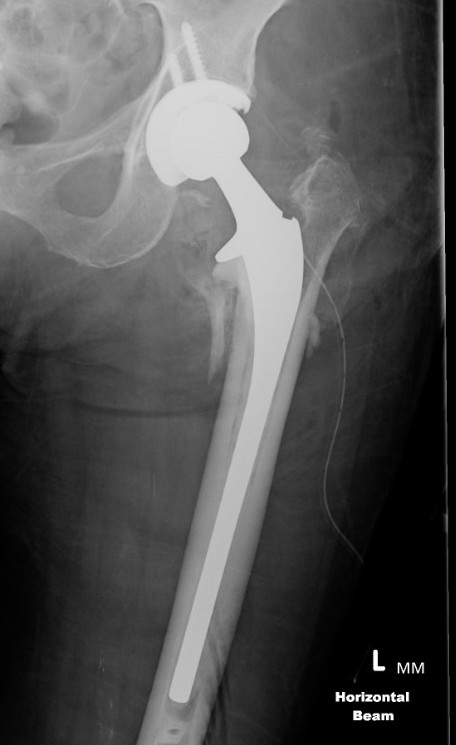

Cephalomedullary nail / Proximal femoral nail

Mechanical advantages

- load sharing rather than load bearing

- decreases lever arm

- supports medial cortex

Surgical advantages

- smaller incision / minimally invasive

- reduced blood loss

- shorter surgical times

Indications

- reverse oblique

- unstable fracture / loss of lateral buttress / loss posteromedial support

- subtrochanteric extension